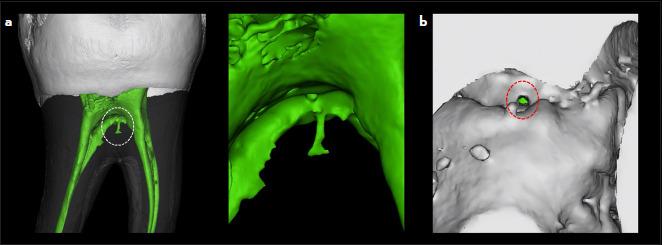

This study investigated the morphology of accessory canals in the mandibular first molar of a Malaysian subpopulation.

METHODS

A total of 140 mandibular first molars were scanned using micro-computed tomography. The accessory canals for each of the mesial and distal roots were classified according to Ahmed et al. system based on location (coronal, middle and apical thirds) and type (patent, blind, loop and delta). A total of thirty mandibular first molar teeth were used for calibration. The Chi-square and Chi-square goodness-fit tests were used to assess the association between the categorical variables. The significance was set at 0.05 (p<0.05).

RESULTS

Results showed that the prevalence of accessory canal is 80.71%. The apical third was the most common location for accessory canals in the mesial (79.3%) and distal (75.9%) roots (p<0.001). Amongst accessory canal types, the patent type was the most common (76.43% and 71.43%, respectively) with the codes of M(A1), D(A1). No significant association was found between root type and the presence of the accessory canals (p=0.071). A significant difference was found in the type of accessory canals and the location within the root (p<0.001).

CONCLUSION

In this population, the mandibular first molars showed a high prevalence of accessory canals in the mesial and distal roots. Patent accessory canals in the apical third are the most common in both roots followed by apical delta. (EEJ-2024-10-163).